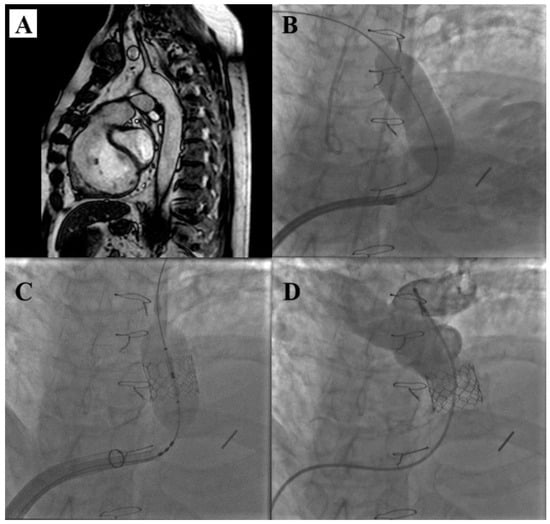

- Zahn, E.M.; Chang, J.C.; Armer, D.; Garg, R. First human implant of the Alterra Adaptive Prestent TM: A new self-expanding device designed to remodel the right ventricular outflow tract. Catheter. Cardiovasc. Interv. 2018, 91, 1125–1129. [Google Scholar] [CrossRef]

- Dimas, V.V.; Babaliaros, V.; Kim, D.; Lim, D.S.; Morgan, G.; Jones, T.K.; Armstrong, A.K.; Berman, D.; Aboulhosn, J.; Mahadevan, V.S.; et al. Multicenter Pivotal Study of the Alterra Adaptive Prestent for the Treatment of Pulmonary Regurgitation. JACC Cardiovasc. Interv. 2024, 17, 2287–2297. [Google Scholar] [CrossRef]